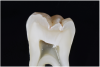

Fig 7. ICDAS code 0: Sectioned tooth confirms stain not indicative of carious penetration of fissure.

Figure 7

To diagnose pit-and-fissure caries, clinically the tooth being assessed should first be wet, and the practitioner evaluates its pits and grooves for any decalcification, which typically presents as a chalky white area that follows the depth of the groove (Figure 10 and Figure 11). This finding with the tooth being wet defines an ICDAS code 2 lesion. Next, the grooves are dried completely using a 5-second air stream, and the clinician notes any areas of chalkiness in the now-dry grooves. Any such area of chalky decalcification noted only after drying would represent an ICDAS code 1 lesion (Figure 8 and Figure 9). Code 1 and/or code 2 lesions are classified as CCS code 1 initial lesion. If no chalkiness is noted in either a wet or dry groove or pit, the tooth structure is classified as sound and documented as ICDAS and CCS code 0 sound structure (Figure 6 and Figure 7). The presence of stain and hypocalcification should be disregarded.